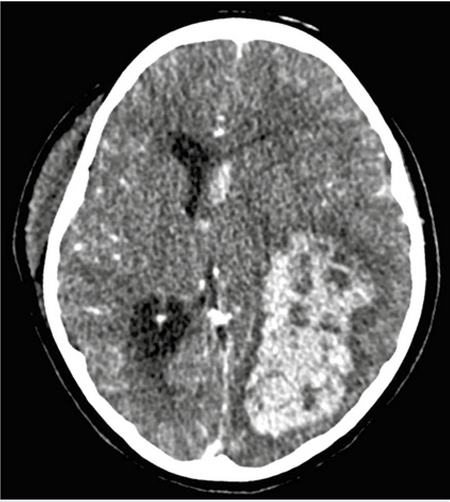

Cinco días después, persistía con fiebre y presentó deterioro neurológico súbito que requirió apoyo mecánico a la ventilación y cuidados intensivos. En el estudio tomográfico se documentó hemorragia aguda intraventricular e intraparenquimatosa (Figura 7). Ingresó a craniectomía descompresiva, drenaje de hematoma (100 mL) y toma de biopsia (Figuras 8 y 9). En las siguientes 2 semanas su evolución no mejoró persistiendo con deterioro neurológico, múltiples sangrados a nivel de sistema nervioso central (Figura 10) y gastrointestinal, así como hemorragia pulmonar masiva con nula respuesta a múltiples intervenciones (i.e.: pulsos de metilprednisolona, inmunoglobulina humana intravenosa, ciclosporina, rituximab, anfotericina B, múltiples transfusiones de hemoderivados, y plasmaféresis). Finalmente presentando falla orgánica múltiple, muerte cerebral y paro cardiorrespiratorio refractario a reanimación cardiopulmonar.

Figura 7 Tomografía axial computada. Se observa hemorragia intraparenquimatosa en región temporo-parieto-occipital izquierda, afectando ventrículo izquierdo con efecto de masa y desviación de línea media.